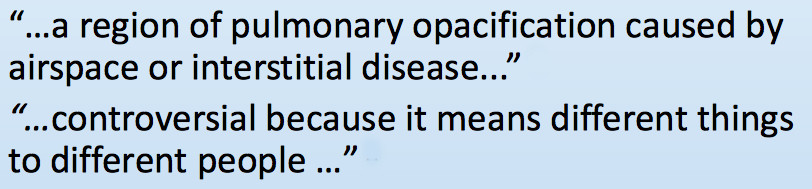

这是一项针对放射科医师有关浸润影代表什么(可多选)的调查 [2]

Radiology.2005;235(1):2-8.

结果显示认为浸润影代表细菌性肺炎、非特异性炎症、间质性肺炎、病毒性肺炎、实变等,五花八门。平均5.7,SD±3.2,中位数6,所以浸润影在临床的操作中会存在一些问题。